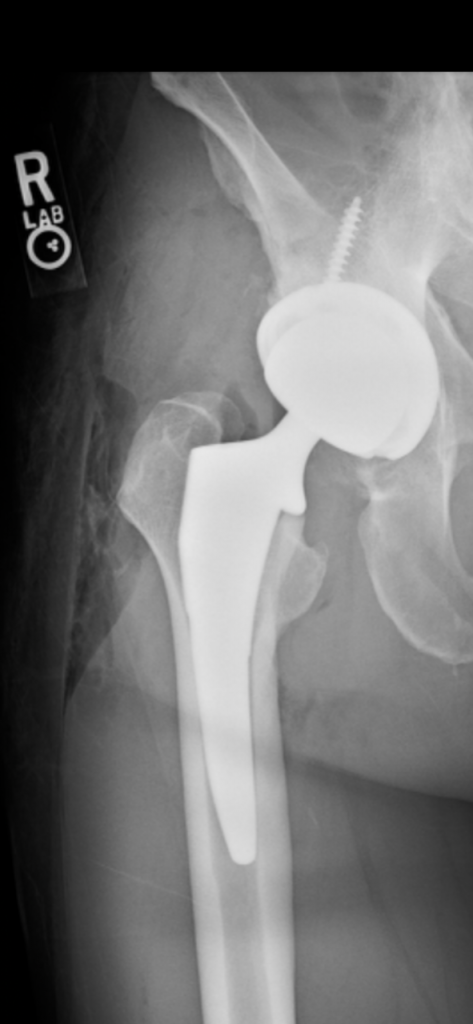

Hip Replacement